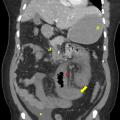

Le diagnostic de TVP récente repose sur l’imagerie. Elle doit être réalisée chez tout patient qui en présente une suspicion clinique. L’échographie-Doppler est généralement l’examen de première intention  ; elle permet la visualisation directe du thrombus dans la veine porte et l’absence de flux au Doppler en cas de TVP complète (sensibilité de 88 à 98  %, spécificité de 80 à 100  %). Elle doit être complétée systématiquement par un scanner (ou une imagerie par résonance magnétique [IRM]) abdominal avec injection de produit de contraste, et aux quatre temps d’acquisition (sans injection, phase artérielle, portale et tardive), si cette imagerie n’a pas été réalisée d’emblée. Le scanner permet de confirmer le diagnostic de TVP, de déterminer le degré d’extension aux veines spléniques et mésentériques, de rechercher un facteur local et des signes d’ischémie mésentérique. De plus, il permet d’identifier des signes d’hépatopathie chronique sous-jacente (dysmorphie hépatique, signes d’hypertension portale) [fig. 2].

Une ischémie mésentérique est recherchée systématiquement sur le scanner abdominal aux quatre temps (sans injection, temps artériel, portal et tardif) et est confirmée par la constatation de signes de souffrance intestinale associés à la TVP tels qu’un épaississement de la paroi intestinale et/ou une diminution de rehaussement des anses après injection de produit de de contraste. La mise en évidence d’une absence de rehaussement pariétal, d’une dilatation intestinale supérieure à 25 mm ou encore d’une pneumatose intestinale voire aéroportie (présence de gaz dans la lumière de la veine porte) sont des signes de gravité évoquant une nécrose intestinale et indiquant un traitement chirurgical.